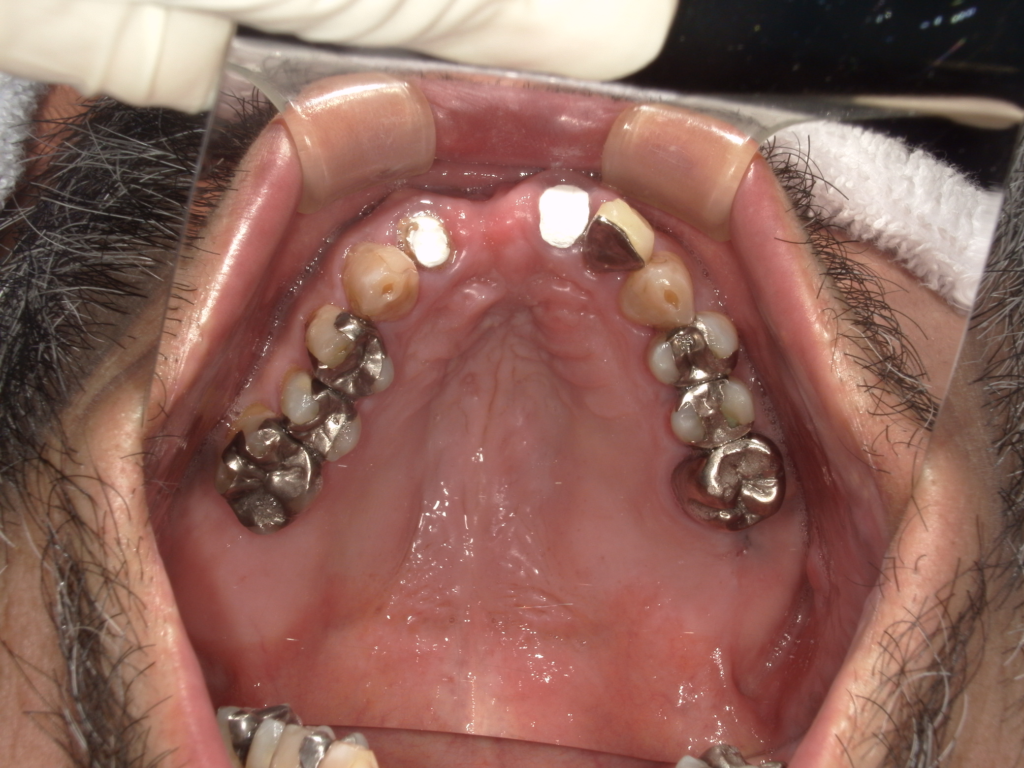

Y様インプラント実例 #44

左の上下の奥歯をインプラントで治療しています。

左下の奥歯は歯を抜くのと同時にインプラントの埋め込みを行っています。

被せものは上下、セラミックスで作っています。

治療前

治療後